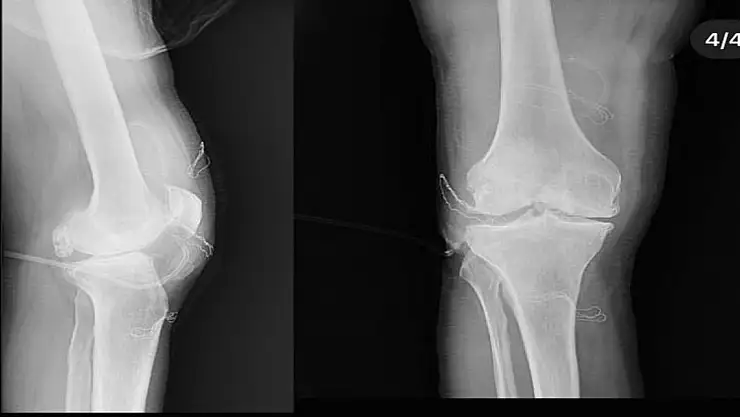

Diz ağrısı şikayeti ile geldiği Düzce Üniversitesi Tıp Fakültesi Hastanesi'nde ameliyata alınan hastanın dizlerinden toplam 41 adet multipl sinovial kondromatozisi çıkartıldı. Özellikle diz eklemi çevresinde görülmekle birlikte kalça, dirsek ve diğer eklemlerde de görülen, ufak parçalardan oluşan cisimler olarak tanımlanan eklem faresi, eklem çevresinde eklem sıvısı ya da sinoviyumda görülen kıkırdak ya da kemik parçalarıdır. Eklem farelerinin boyutları birkaç milimetreden birkaç santimetreye kadar çıkabiliyor.